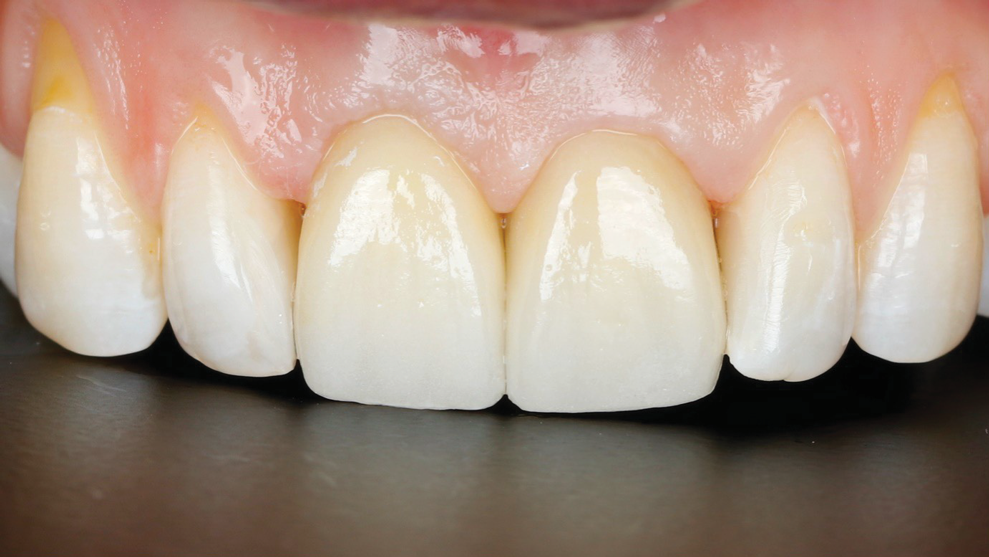

Fig 16. SPOT Step 7: The provisional restoration with an “S”-shaped subgingival configuration is fabricated.

Figure 16

Fig 17. SPOT Step 7, cont’d: A screw-retained provisional restoration or custom-made healing abutment is placed to create a proper emergence profile. Passive fit should be confirmed with an x-ray.

Figure 17

Step 7- Restoration:A provisional crown restoration or custom healing abutment is placed (Figure 16 and Figure 17). A radiograph is taken to confirm adequate placement of the implant.